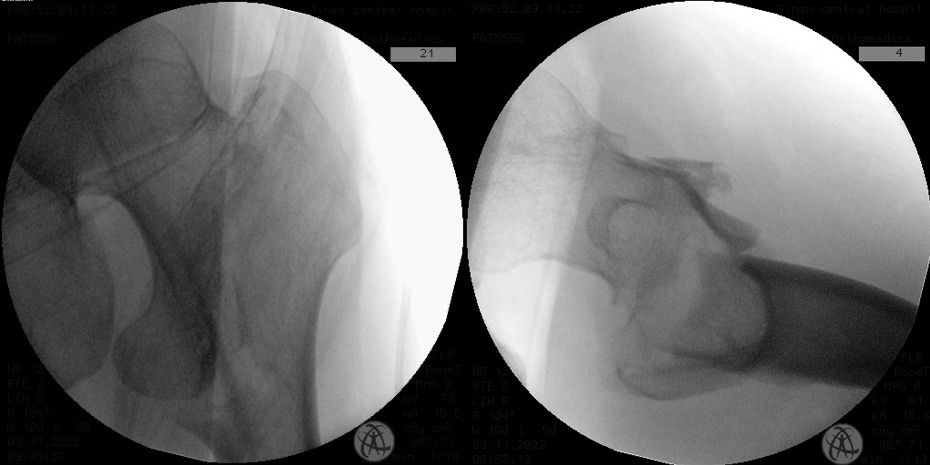

全功能智慧医院患者范先生骑电动车不慎摔伤左髋部,当时即感左髋部肿痛,活动受限,拨打120由急救车送到我院急诊外科,拍片检查结果示左股骨转子间骨折,随即收入创伤中心准备行手术治疗。林涛副主任医师根据患者术前X线及CT三维重建检查结果分析,患者左股骨转子间骨折股骨转子间骨折为OTA/AO分型中的A2.3型,骨折断端前后移位明显,是一种复杂的骨折类型,复位较为困难。

难复性股骨转子间骨折真实面目是X线片正位骨折对位可以接受,侧位骨折矢状位不稳,骨折近端向前方、骨折远端向后方成角移位,该患者更为复杂的是骨折断端前方有游离骨折片,常规钳夹复位方式可能会导致骨折片异常嵌插或再骨折。高长虹主任医师、林涛副主任医师团队经过周密仔细的术前讨论和准备,如期为患者行手术治疗,术中采取骨折近、远端分别予以微创复位方式,完成髓内钉内固定手术,X线正、侧位骨折对位对线良好,骨折断端前方骨折片位置良好,术中及术后后透视图像如下:

*术中